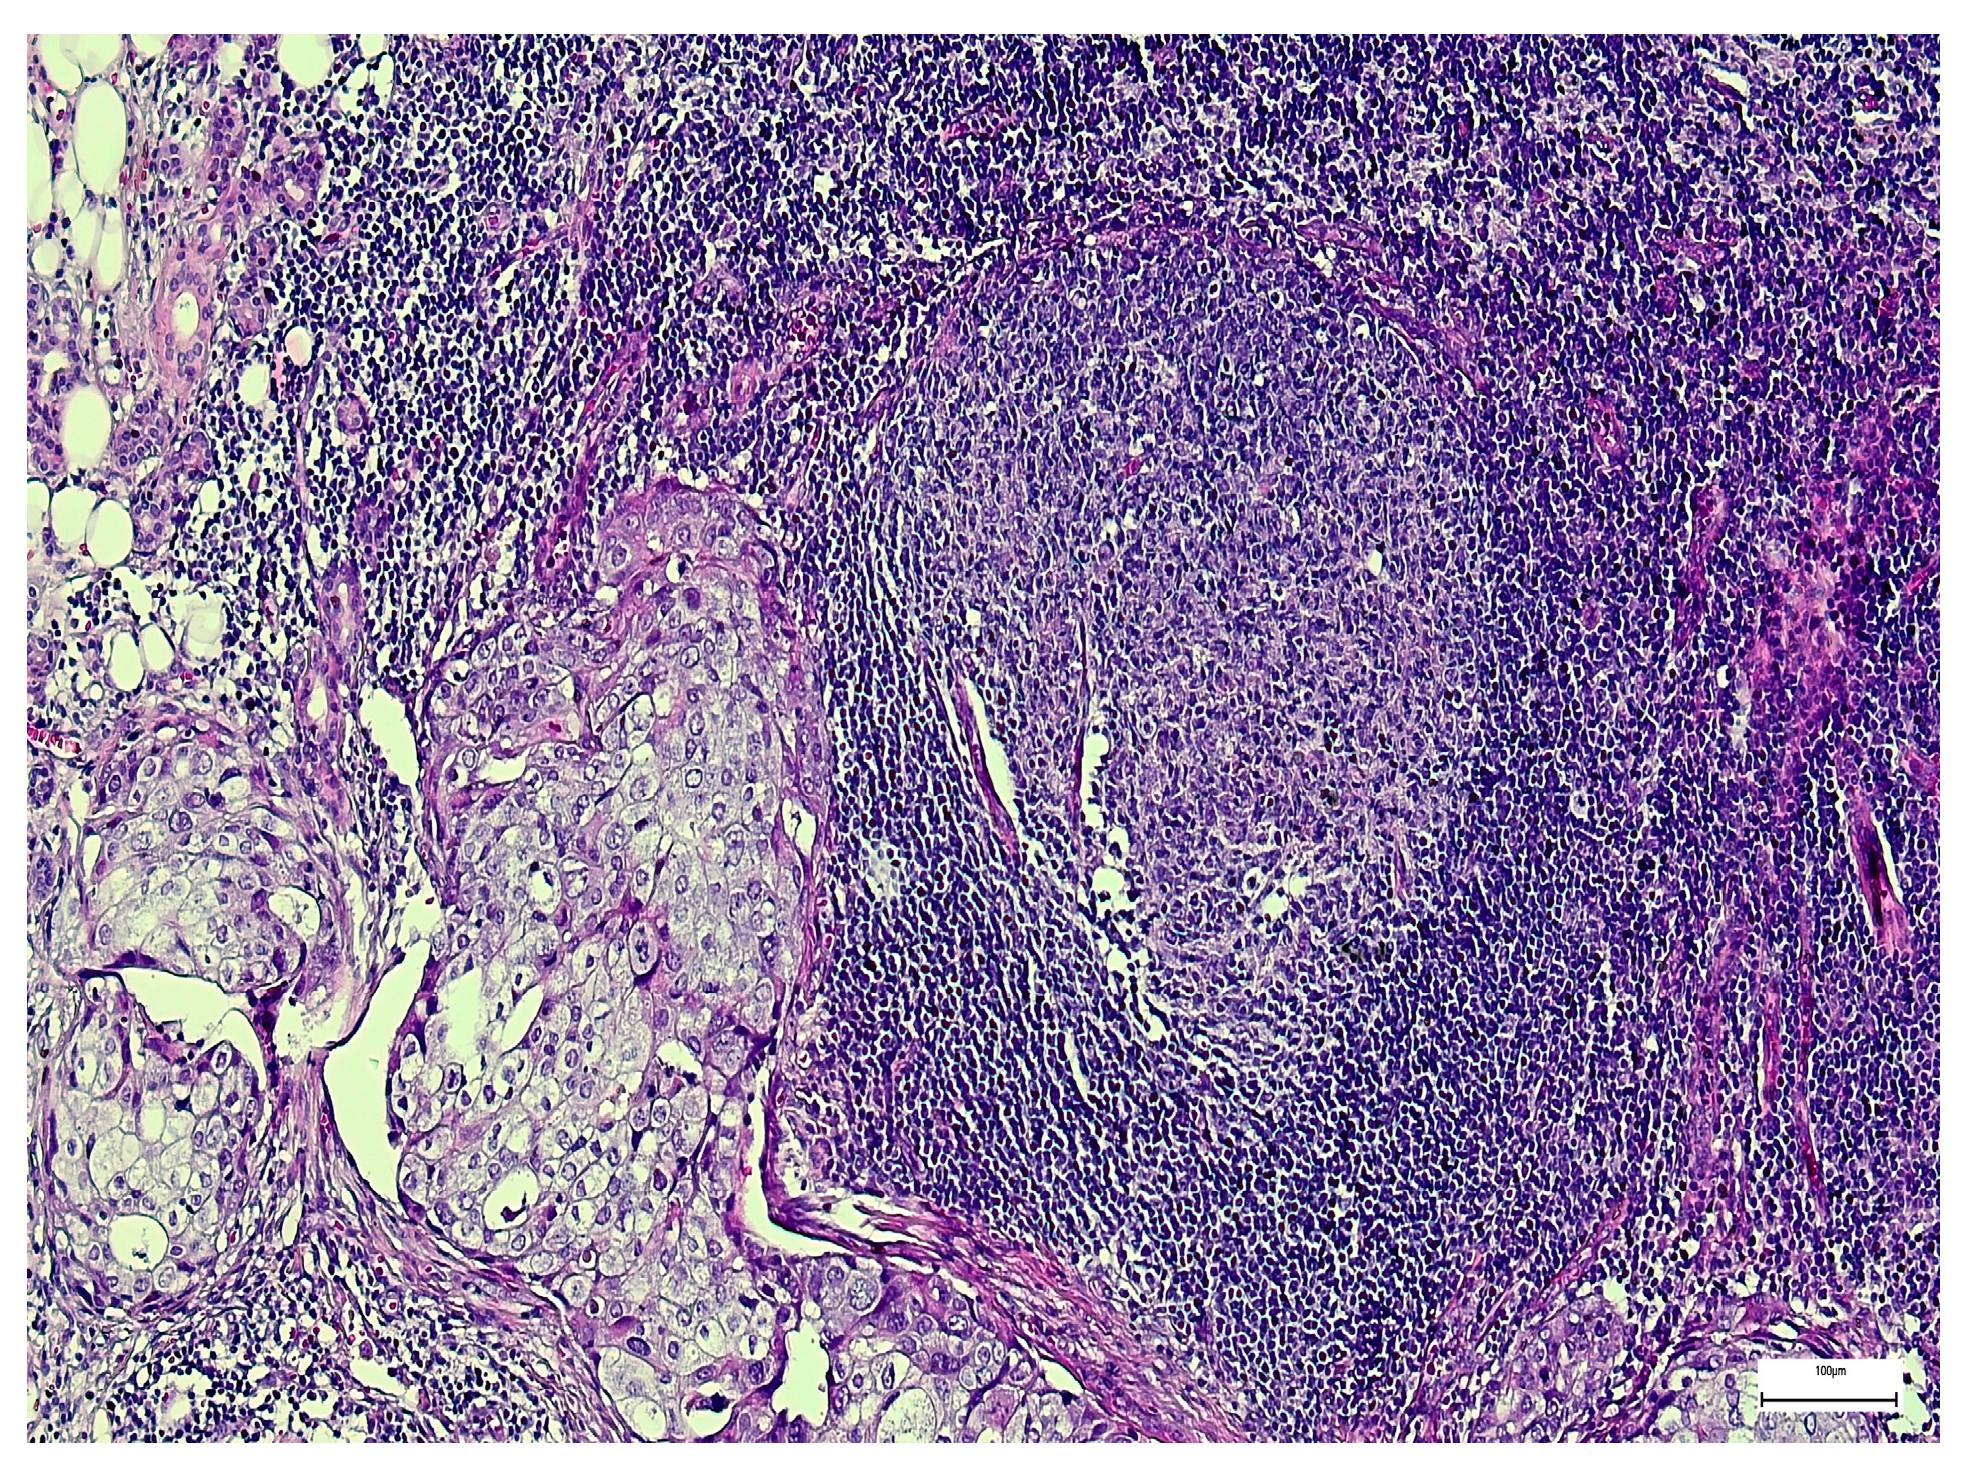

3. Results

3.2. Qualitative and Semi-Quantitative Assessment of SOX-2 and EZH-2 Immunoexpression